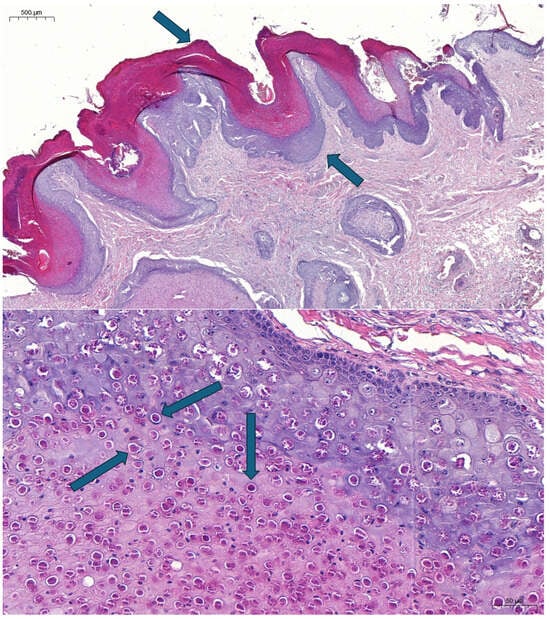

3.1. Histopathology and Laboratory Diagnosis